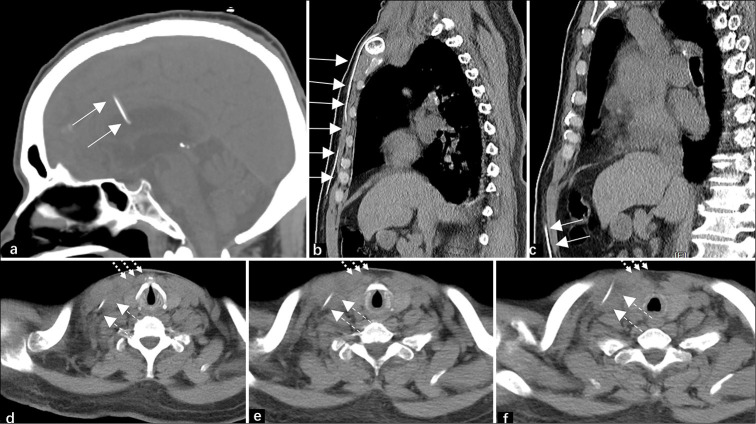

Ventriculoperitoneal (VP) shunts are commonly used to treat hydrocephalus by diverting cerebrospinal fluid from the ventricles to the peritoneal cavity. Migration of the VP shunt into the heart and pulmonary artery is a rare complication. Herein, we described a 67-year-old man with a VP shunt catheter that migrated through the venous system into the pulmonary circulation, highlighting early diagnosis with imaging and symptoms.

脑室-腹膜(VP)分流术通常用于脑积水的治疗,将脑脊液从脑室转移到腹膜腔。副静脉分流移入心脏和肺动脉是一种罕见的并发症。在此,我们描述了一位67岁的男性患者,他的VP分流导管通过静脉系统进入肺循环,强调了早期诊断的影像学和症状。